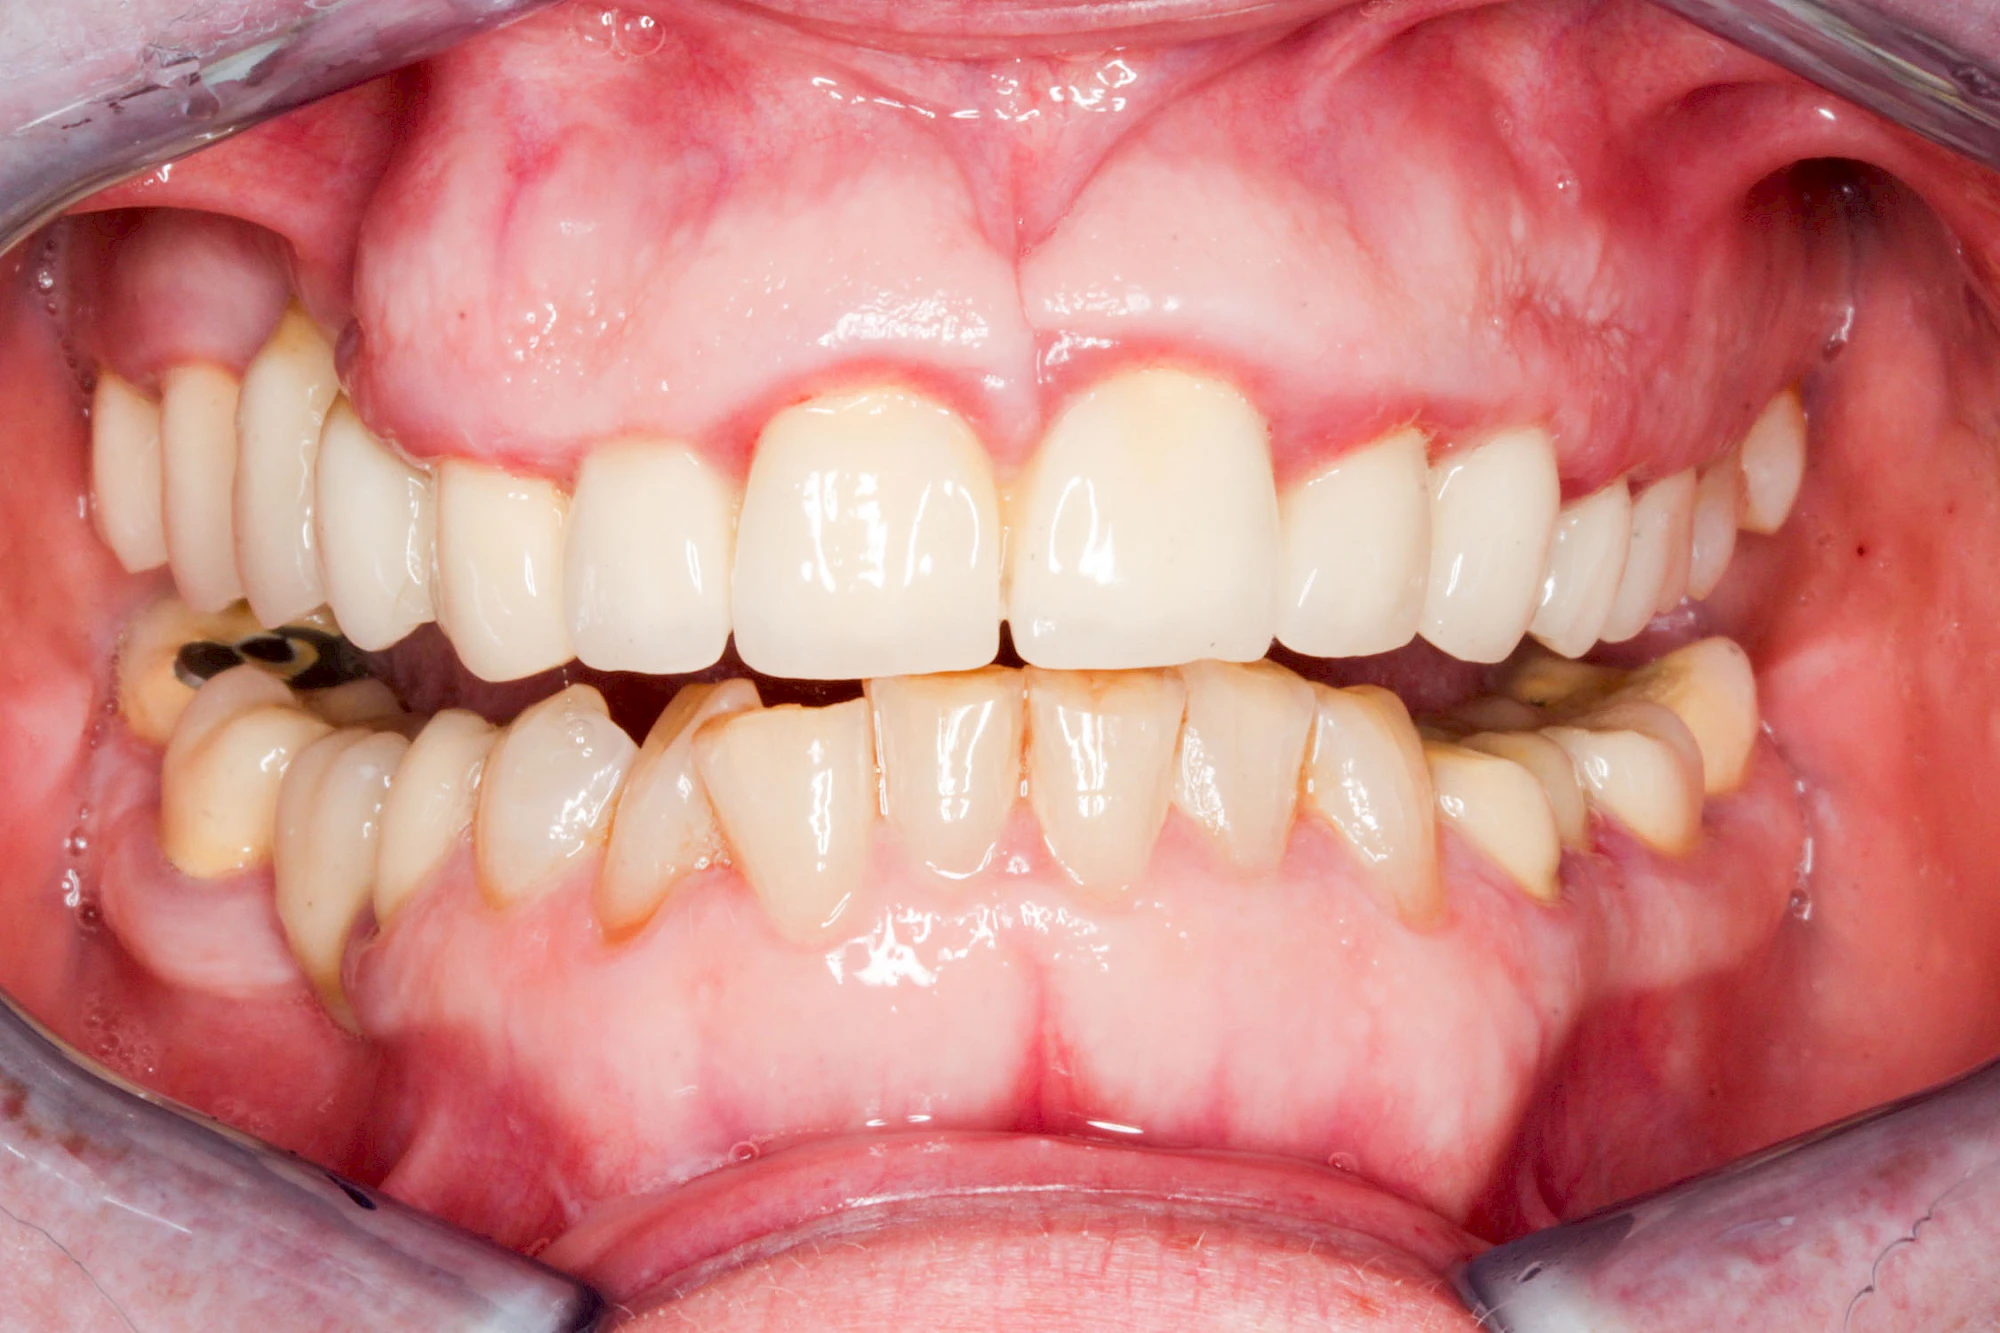

Ist zunächst nur das Zahnfleisch von der Entzündung betroffen, spricht man von Gingivitis. Später, wenn auch der Knochen um die Zähne herum entzündet ist, spricht man von einer Parodontitis. Bei der Parodontitis wird der Knochen nach und nach abgebaut und das Zahnfleisch zieht sich zurück. Die Zahnhälse und Zahnwurzeloberflächen liegen mehr und mehr frei. Die Zähne werden zunehmend lockerer und fallen schließlich aus.